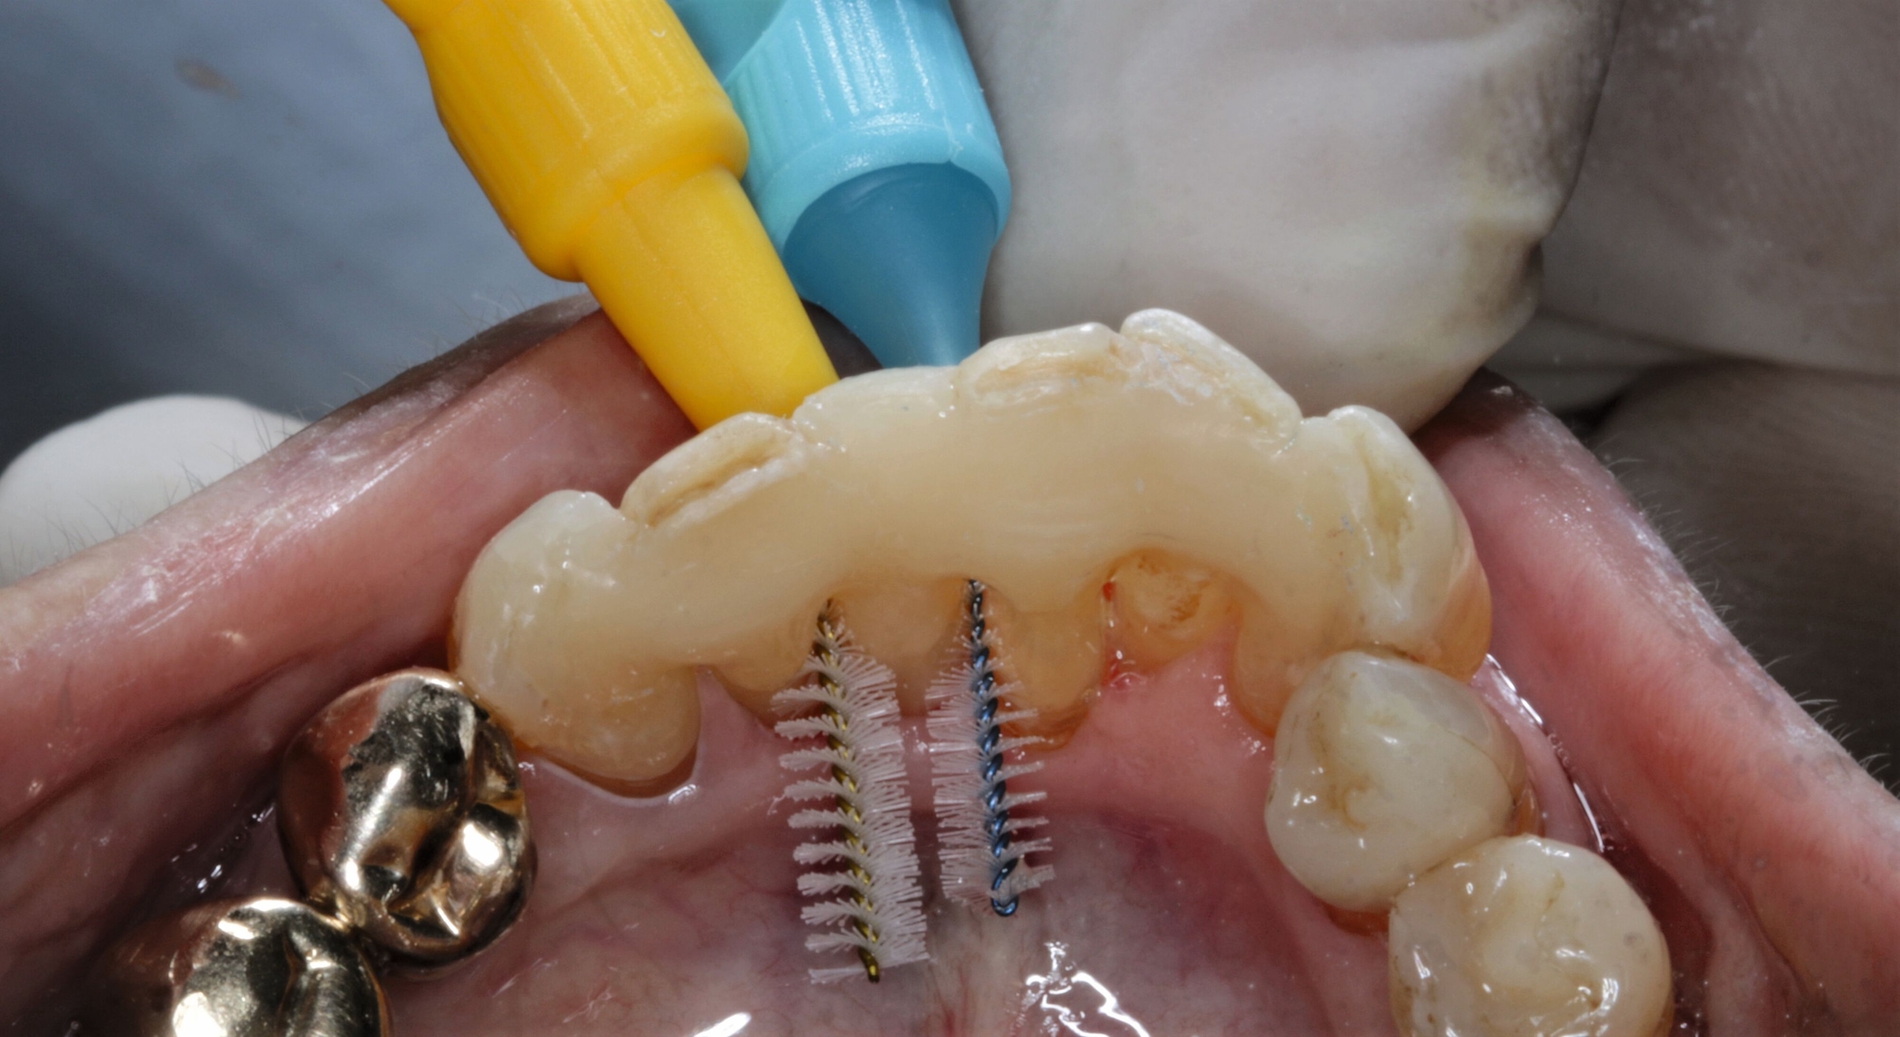

Um bei der adhäsiven Befestigung des Kunststoff-Prothesenzahns das Risiko einer Speichelkontaminierung zu reduzieren, wurde Kofferdam verwendet. Die Interdentalräume wurden mit einer elastischen Befestigungsschnur (Wedjets, Coltene) blockiert, um ein späteres Ausfließen der Interdentalräume mit Komposit zu verhindern – einerseits um weiterhin eine gute häusliche Mundhygiene zu ermöglichen, andererseits um keine unnötig langwierige Nacharbeitung bei der Entfernung von überschüssigem Komposit zu verursachen (Abbildung 9).

Anschließend wurde die unpräparierte Zahnoberfläche mittels 35-prozentiger Phosphorsäure (Ultra Etch, Ultradent) 60 Sekunden lang geätzt, mit einem Zwei-Komponenten-Adhäsivsystem (Optibond FL, Kerr) vorbereitet und das zur Schienung verwendete Polyethylenband (Ribbond THM Adhäsiv Verstärkungsband, Ribbond Inc.) mit Komposit (CeramX Spectra STHV & ST flow, Dentsply Sirona) fixiert. Die Polyethylenband-Oberfläche wurde großzügig mit Komposit überdeckt, ebenso wurden die Zähne mittels Komposit deutlich verblockt, um eine möglichst hohe Stabilität der Schienung zu erreichen. Gleichzeitig wurde weiterhin darauf geachtet, dass die Hygienefähigkeit der Interdentalräume erhalten bleibt (Abbildung 10).